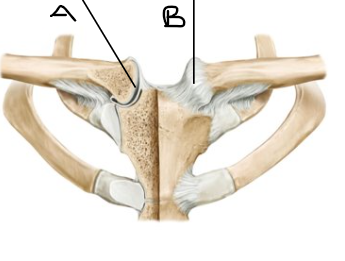

what is letter A? (joint)

sternoclavicular joint

what is letter B? (joint)

sternoclavicular ligament

what is letter A (joint image)

AC ligament

what is letter B (joint image)

acromion

what is letter C (joint image)

clavicle

what is letter D? (joint image)

CC ligaments